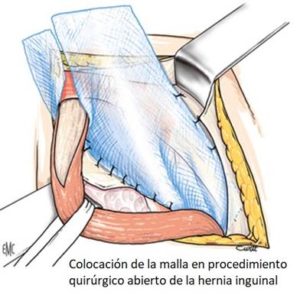

La cirugía de la hernia inguinal, desde el origen de su tratamiento quirúrgico a finales del siglo XIX y durante todo el siglo XX, se ha realizado accediendo a la región inguinal por delante, es decir, incidiendo la piel en la misma región inguinal donde abulta la hernia y se va profundizando hasta llegar al defecto herniario que se repara por esta vía. Es lo que se llama cirugía abierta o por vía anterior de la hernia inguinal.

- En la cirugía abierta por lo general, la duración de la operación es algo menor y el gasto sanitario es también algo más reducido. Este tipo de consideraciones son importantes en la gestión sanitaria, especialmente donde la presión asistencial es enorme como ocurre en la sanidad pública.

Como se ha dicho, la cirugía tradicional de la hernia por vía anterior conlleva una larga convalecencia debido al dolor postoperatorio que exige, para su tratamiento, además del consumo de analgésicos, un nivel de reposo considerable, a veces incluso absoluto, que casi siempre se extiende entre 1 o 2 meses. En algunas ocasiones incluso alguna semana más para recuperarse plenamente.

Como se ha dicho, la cirugía tradicional de la hernia por vía anterior conlleva una larga convalecencia debido al dolor postoperatorio que exige, para su tratamiento, además del consumo de analgésicos, un nivel de reposo considerable, a veces incluso absoluto, que casi siempre se extiende entre 1 o 2 meses. En algunas ocasiones incluso alguna semana más para recuperarse plenamente.

Consecuencia de lo cual, retrasa considerablemente la incorporación del paciente a su actividad laboral o actividad física rutinaria.

Consecuencia de lo cual, retrasa considerablemente la incorporación del paciente a su actividad laboral o actividad física rutinaria.

La cirugía abierta por vía anterior tendrá todavía aun sus ocasionales indicaciones. Pacientes con gran obesidad, hernias inguinales de tamaños extremos o pacientes con múltiples procedimientos quirúrgicos previos que conllevan múltiples adherencias que impidan la laparoscopia.